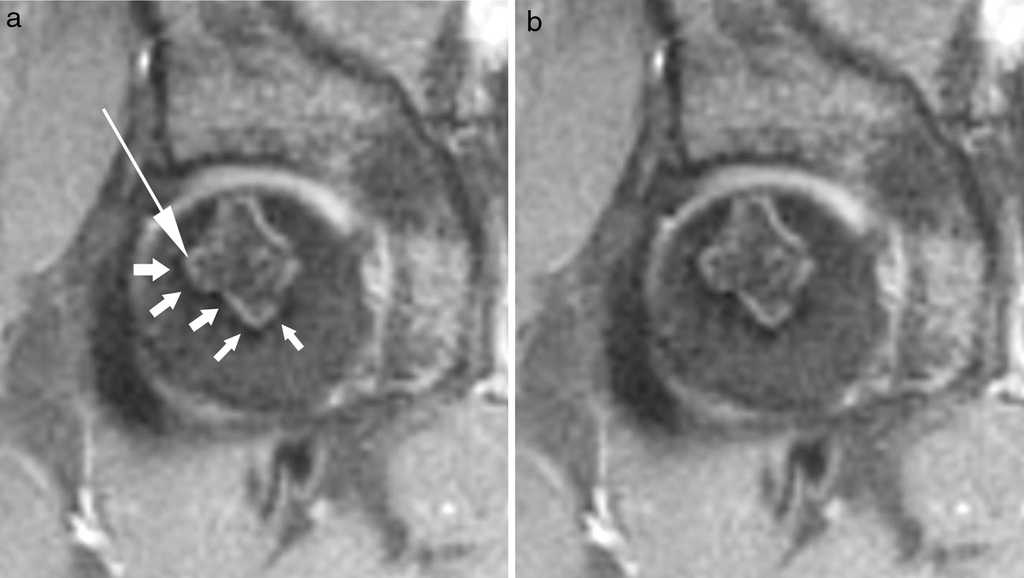

Este signo se observa, mediante la resonancia magn??tica (RM) con tiempo de repetici??n largo, como dos im??genes lineales adyacentes entre s??, de trazo serpiginoso, delimitando la interfase entre el hueso necr??tico y el normal: una banda hipointensa externa define el hueso normal y corresponde a tejido fibr??tico y esclerosis, mientras que la otra banda, hiperintensa, tiene una localizaci??n interna, delimita el hueso necr??tico y representa tejido de granulaci??n hipervascular de reparaci??n de la zona de necrosis2,3 (figs. 1 y 2).

El signo de la doble l??nea es importante en el diagn??stico de la necrosis avascular. A pesar de que existen otros signos descritos por radiolog??a simple, tomograf??a computada y RM, este es el de mayor especificidad. Una vez diagnosticado el proceso, dado que el signo permite diferenciar claramente el hueso necr??tico del normal, resulta esencial en la clasificaci??n, planificaci??n terap??utica y seguimiento. Su presencia permite valorar la localizaci??n, extensi??n, morfolog??a y volumen del hueso necr??tico, susceptible de tratamiento y control.

Como conclusi??n, el signo de la doble l??nea es caracter??stico de la osteonecrosis y permite diferenciar claramente el hueso necr??tico del normal. Por este motivo, su presencia es fundamental en el diagn??stico, despistaje, planificaci??n terap??utica y seguimiento.